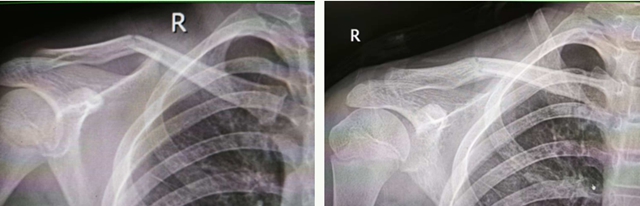

左:复位前 右:复位后

其中,15岁的小林伤势最为严重,骨折为粉碎性,多个骨碎片游离,骨折断端移位明显,并有戳破皮肤趋势。

另外2名少年虽然也同时出现锁骨骨折,只是病情相对较轻,骨折端移位相对不大。

小林的锁骨骨折最为严重,为粉碎性,若行开放手术,不仅手术切口大,出血多,钢板内固定后还可能影响骨骼后续生长。传统中医手法正骨具有不开刀、不出血、不留疤、费用低等特点。医生运用“推端提按、抱迫靠拢”等正骨手法,蓄力指尖,擒拿扶正,将分散的骨折碎片精准拼接、复位;再用杉树皮小夹板固定,既牢牢锁住骨折端避免再次移位,又不压迫局部皮肤导致皮肤溃疡;同时辅以医院自制的消肿止痛中药外敷,辅以活血化瘀内服方剂,促进骨痂生长和创伤修复。

另外2名少年锁骨骨折轻度移位,病情相对缓和,团队同样采用“手法复位+8字绷带固定”的经典中医方案,快速完成复位固定后,同样施以中药外敷调理,有效缓解疼痛肿胀,促进骨折愈合。